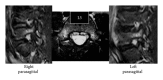

Spondylolysis is reported as a stress fracture of the pars interarticularis with a strong hereditary basis. Three cases of lumbar spondylolysis in juveniles from the same family are reported, and the genetics of the condition are reviewed. The first boy, a 13-year-old soccer player, was diagnosed with terminal stage L5 bilateral spondylolysis with grade 1 slippage. The second boy, a 10-year-old baseball player, had terminal stage right side unilateral spondylolysis. The third boy, also a 10-year-old baseball player, was diagnosed with early stage bilateral L5 spondylolysis. The second and third boys are identical twins, and all three cases exhibited concomitant spina bifida occulta. Lumbar spondylolysis has a strong hereditary basis and is reported to be an autosomal dominant condition.